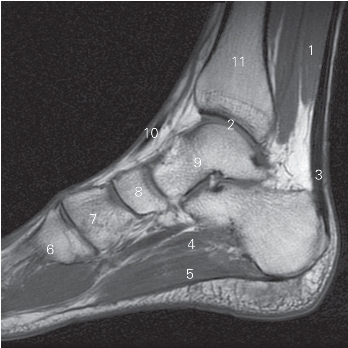

图5-57 经第一跖骨的矢状断层MR T1加权图像

1 比目鱼肌 soleus 2 踝关节 ankle joint

3 跟腱 achilles tendon 4 足底方肌 quadratus plantae

5 趾短屈肌 flexor digitorum brevis

6 第1跖骨 1st metatarsal bones

7 内侧楔骨 medial cuneiform bone

8 足舟骨 navicular bone 9 距骨 talus

10 胫骨前肌 tibialis anterior 11 胫骨 tibia